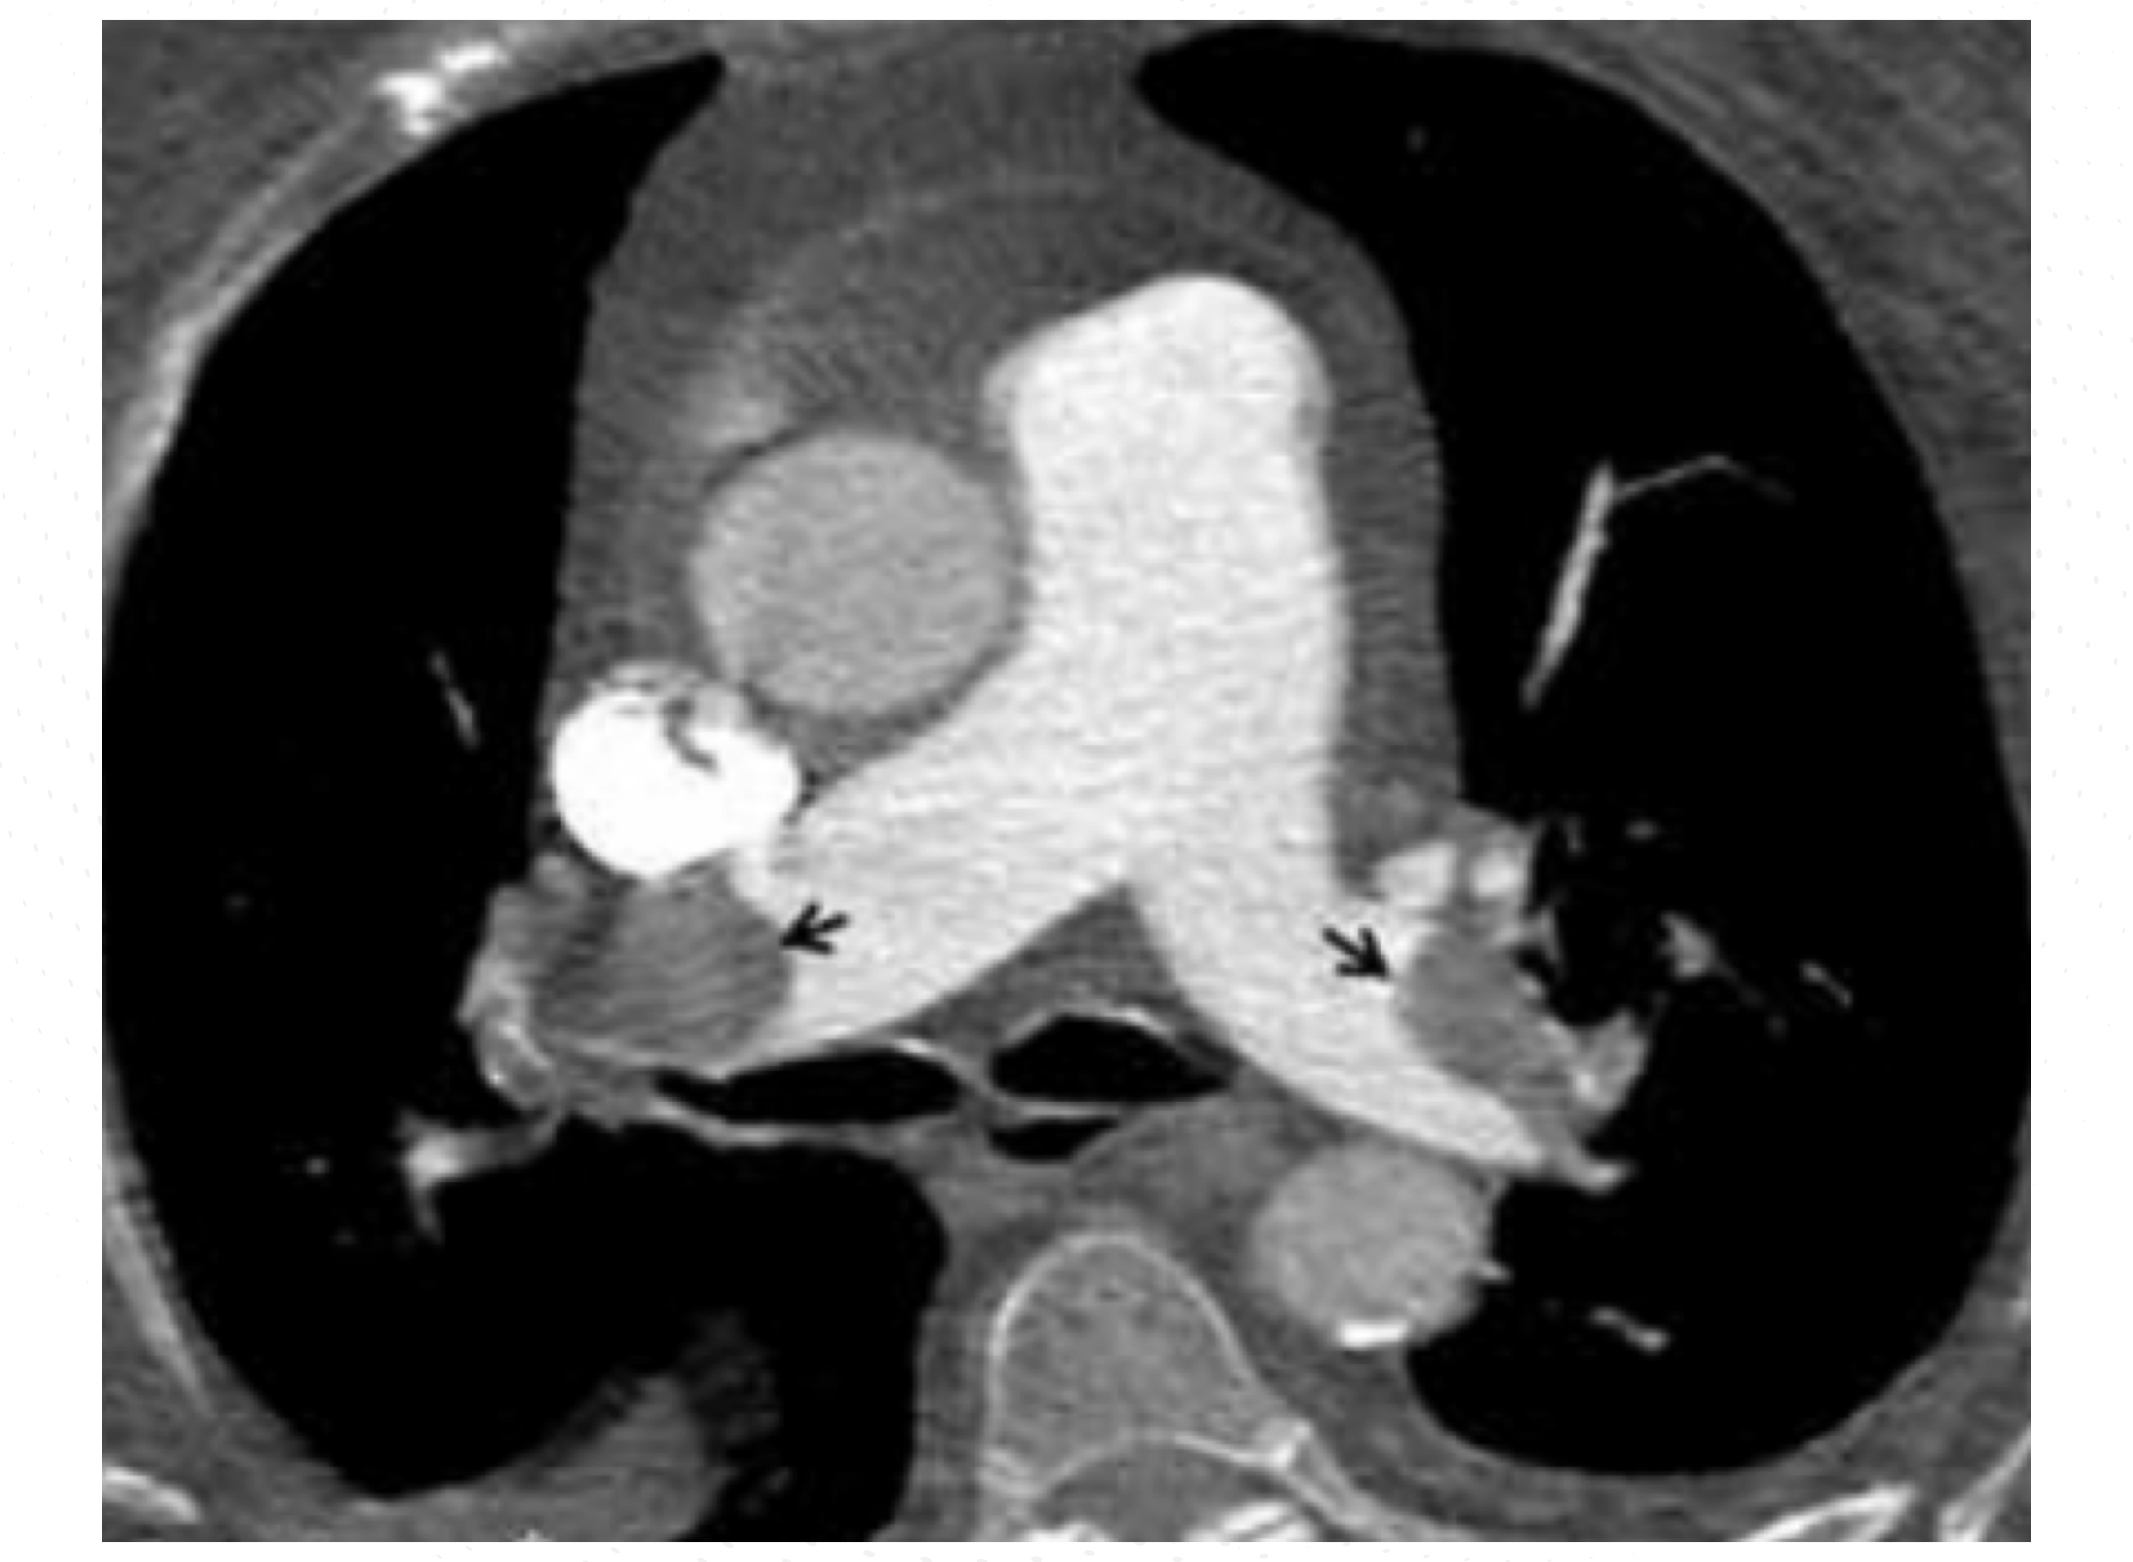

Inició tratamiento con radioterapia y temozolomida concurrente. Durante el transcurso de esta terapia, acudió al Servicio de Urgencias por disnea de instauración súbita, sin alteración hemodinámica ni insuficiencia respiratoria. A la exploración no se apreciaron signos de trombosis venosa profunda en las extremidades. La angiotomografía axial computarizada (angio-TAC) pulmonar confirmó el diagnóstico de un tromboembolismo en la arteria pulmonar principal y bilateral (Figura 1).